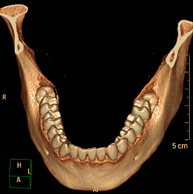

Prueba radiológica que consiste en obtener imágenes de los huesos maxilares de alta definición anatómica (piezas dentarias, trayecto del nervio dentario), mediante el empleo de un equipo de TC (Tomografía Computarizada). Indicaciones: estudio previo a la extracción dental, estudio previo a implantes, tumores, absceso. - TC Senos paranasales